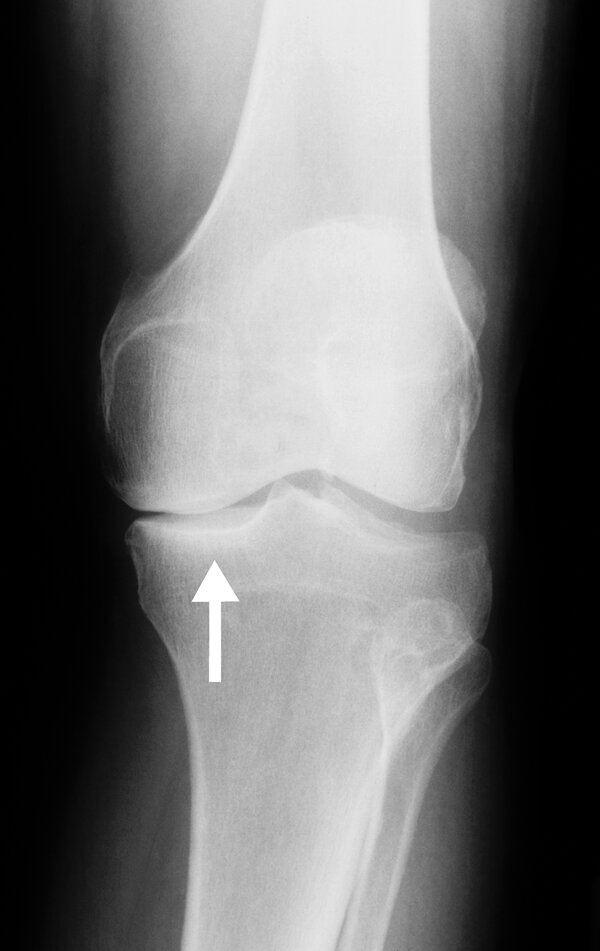

A 42F develops osteoarthritis as seen below. What are secondary causes of OA (name 1) that she should also be tested for?

What is: Hemochromatosis, Wilson's dx, gout, obesity, RA, previous trauma

Secondary osteoarthritis (OA) should be suspected when OA occurs at an early age or involves joints not typical for OA.

joint-space narrowing and subchondral sclerosis consistent with?

OA